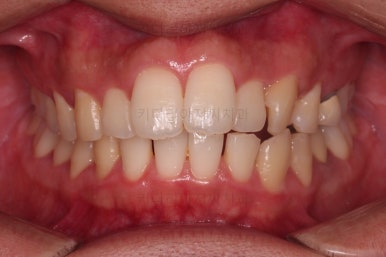

오늘 부산앞니교정 키다리아저씨치과에서 소개해 드릴 환자분은 앞니 사이에 틈이 벌어지고, 앞니가 뻐드러져 있었던 환자분입니다.

초진 시 입안의 모습입니다.

부정교합이 있고요.

또한 눈에 띄는 모습은 앞니가 튀어나오고, 사이사이 틈새가 보인다는 점이에요.